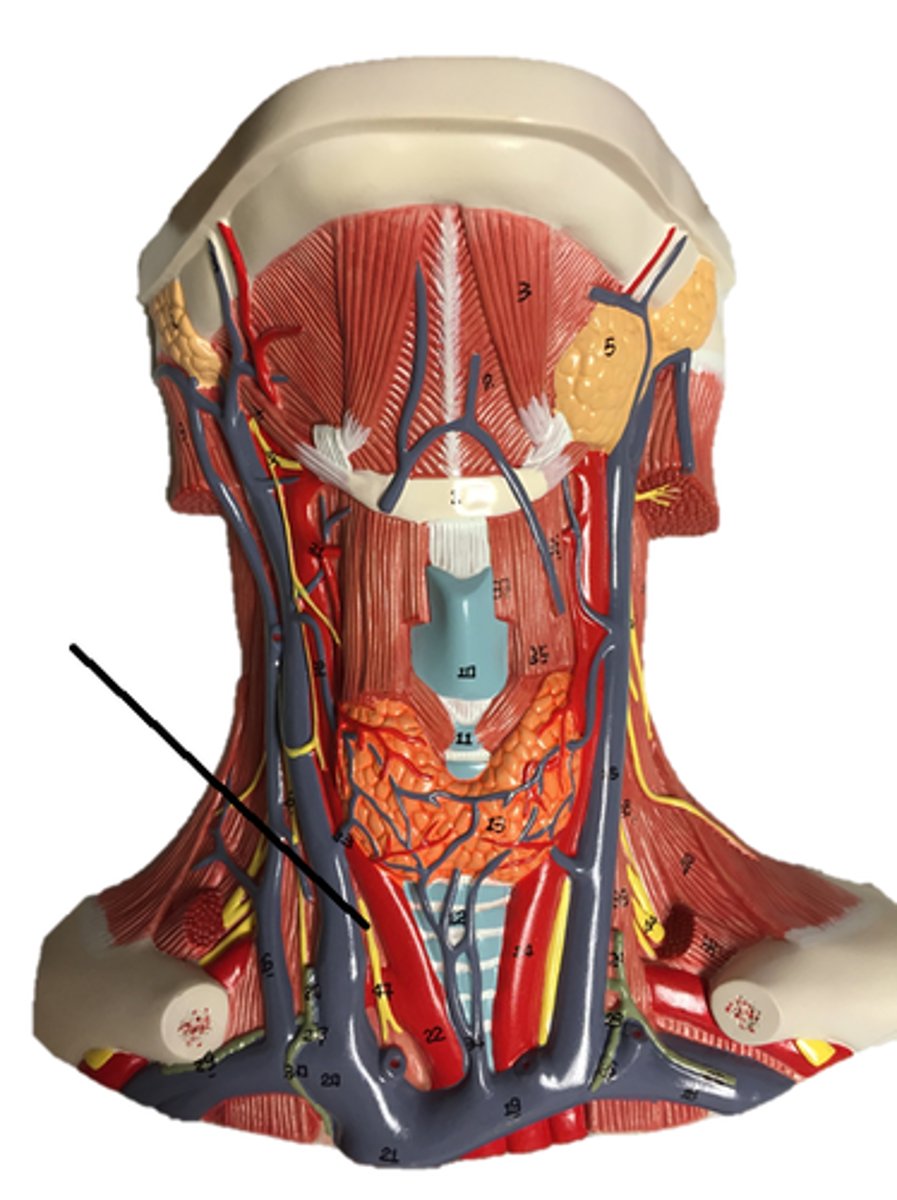

vagus nerve

accessory nerve

hypoglossal nerve

glossopharyngeal nerve

facial nerve

trigeminal nerve